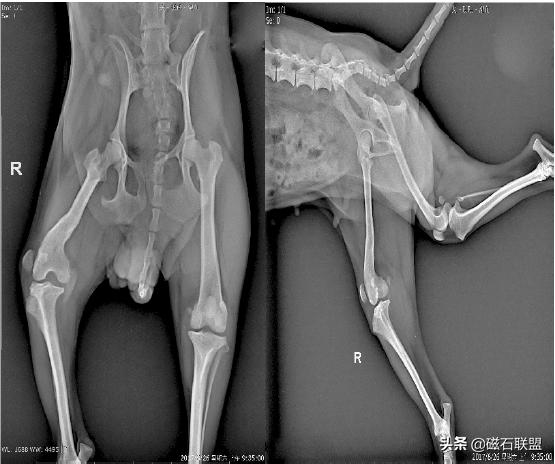

下面就将举一个髌骨脱位的病例来具体说明:

宠物名称:耀耀,品种:泰迪犬,性别:母,年龄:七岁,体重:3kg。

主述:几个月前从桌子上摔下后有单腿跳行的行为,最近发现后肢走路明显跛行,特此就医。

X射线检查:

影像学检查诊断为右后肢髌骨外脱位,与主人协商后决定进行手术。